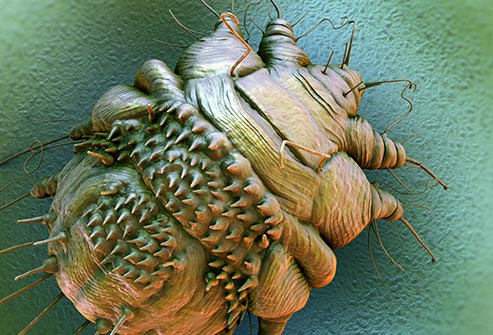

![]()

مرض